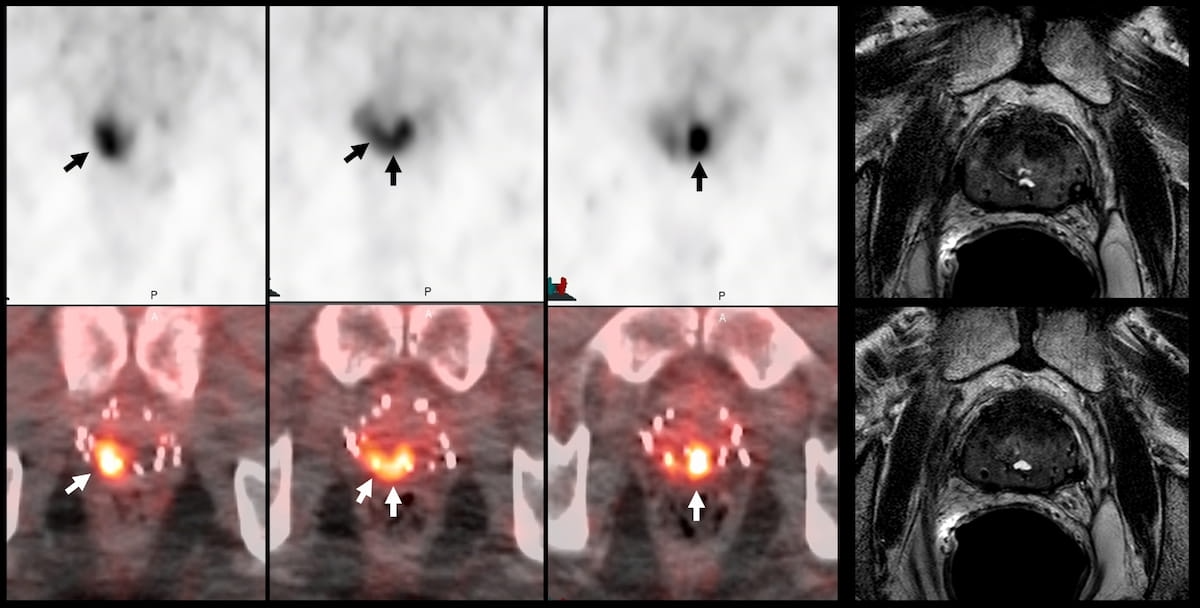

In the above images, the use of 18F-DCFPyL PET/CT reveals several abnormal foci while multiparametric MRI was negative in a 70-year-old patient who had biochemical recurrence nine years after previous treatment for prostate cancer. (Images courtesy of the Society for Nuclear Medicine and Molecular Imaging (SNMMI)).